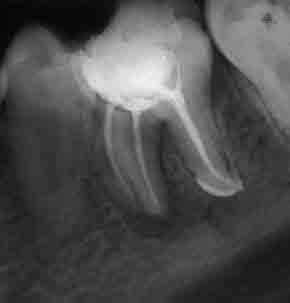

Ендодонтия